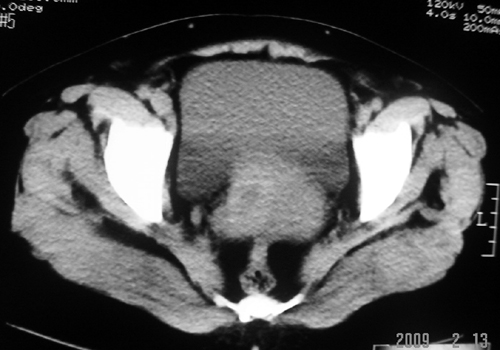

以下是引用余辉在2009-2-14 8:37:00的发言:[br]宫颈左后壁见较大低密度肿物影且向左后上方突出,宫腔内见大片状低密度区,考虑宫颈肿瘤,宫颈癌可能性大,伴宫腔积液或转移